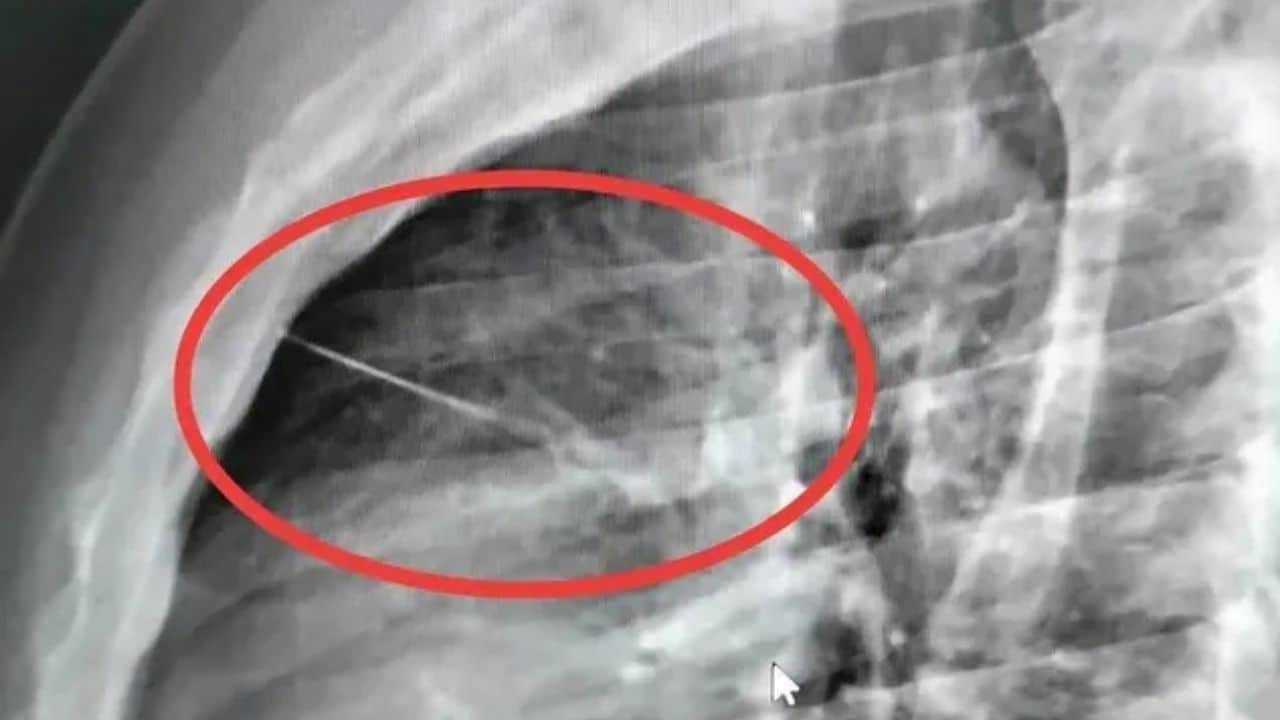

Hospital staff carried out an X-ray and found a small sharp object inside his body near his heart. The item was later identified as a needle about seven centimetres long. Boonlert was then transferred to Buriram Hospital for surgery, with doctors describing the procedure as complex and high-risk.